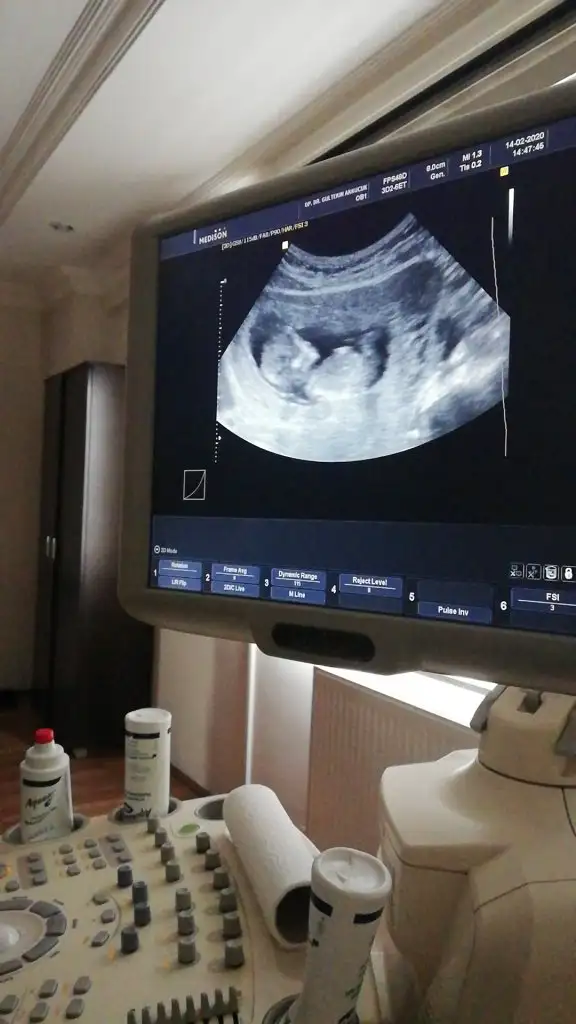

dr soylemeden siz gorun genital nub teorisi ( bebegin cinsiyeti)

Merhabalar Tahmin yorumlarınızı heyecanla takip ediyorum. Bende sabırla 12. haftamızın dolmasını bekledim. Bir yorumda benim için yaparmısınız Buğün 12+1 olduk.

Bacak arası nubuda dik görünüyor erkek 11+2 dimi usg 12+ yada 13 olursa paylaşın A Aryaam